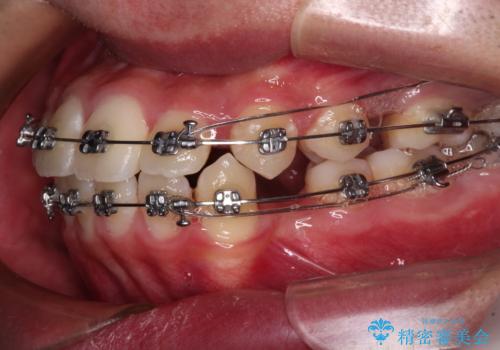

- 矯正装置

- メタルブラケット

- 3年6ヶ月

- 治療回数

- 30回以上

第二小臼歯抜歯により治療期間が長くなることを了承いただき、治療を開始しました。